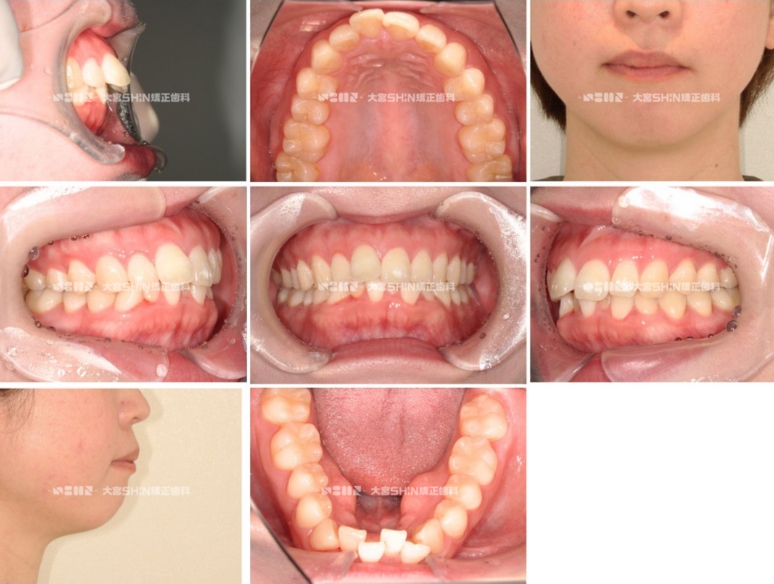

Before

After

主訴 以前他院でマウスピースで部分矯正を行ったが、ガタガタと出っ歯が気になる

診断名 叢生

初診時年齢 30歳

使用装置 ワイヤー矯正(ホワイトワイヤー)

抜歯部位 上下左右第一小臼歯

治療期間 2年3ヶ月

費用 ¥780,000(税込¥858,000)

リスク副作用 痛み、歯根吸収、歯肉退縮、むし歯、後戻り※症例は一例です。結果には個人差があります。